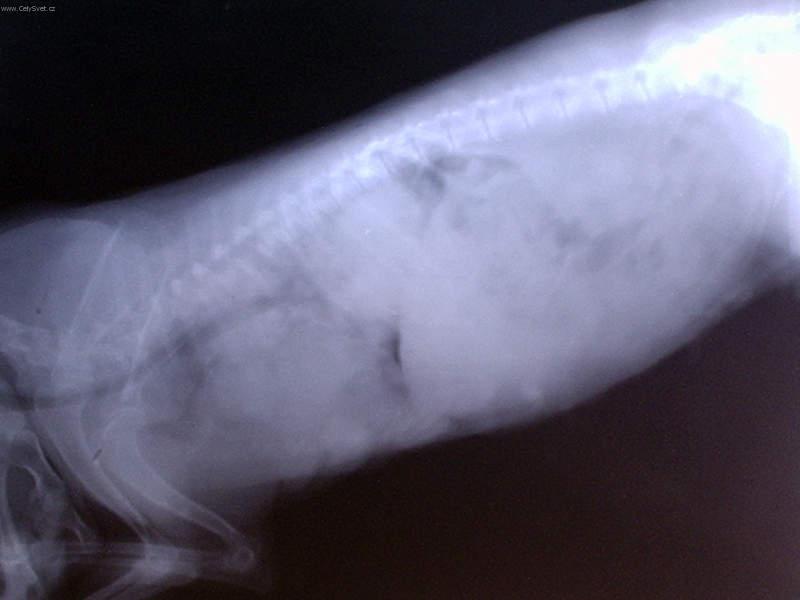

Foto: Onkologie - Novotvary mléčné žlázy u fen

Fotogalerie > PSÍ SVĚT: Veterinární poradna > Onkologie - Novotvary mléčné žlázy u fen